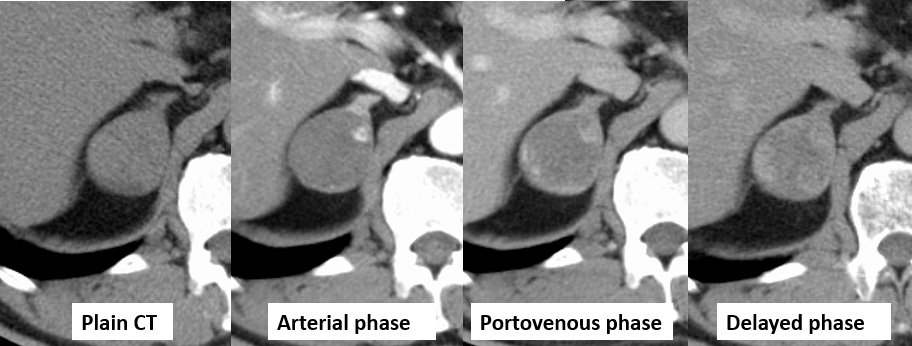

No.98症例4:50歳代 男性

診断:副腎血管腫

【画像所見】

• 境界明瞭、石灰化なし

• 辺縁に結節状の早期濃染を認め遷延性に造影効果の増強を認める

• 境界明瞭

• 肝血管腫同様、dynamic 造影検査にて辺縁のスポット状の造影効果

• 辺縁から中央へ造影効果は遷延する(しないこともあり)

• 病変内部に出血、壊死、線維化を伴う場合、肝の海綿状血管腫のような腫瘍全体の濃染はみられないことが多い

• 腫瘍の辺縁にスポット状の造影効果が認められることが血管腫を疑う手がかりとなりうる